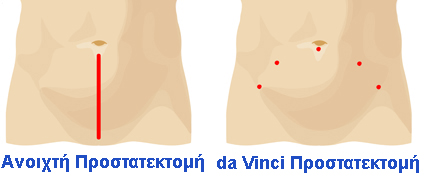

Κατά την ρομποτική προστατεκτομή 5 μικρές οπές μικρότερες του ενός εκατοστού πραγματοποιούνται στην κάτω κοιλιά μέσα από τις οποίες περνούν ειδικοί σωληνίσκοι (τα λεγόμενα τροκάρ) οι οποίες επιτρέπουν την ταχεία είσοδο και έξοδο των λαπαροσκοπικών και ρομποτικών εργαλείων στο εσωτερικό της κοιλιάς του ασθενή.

Η da Vinci Ριζική Προστατεκτομή για την θεραπεία του καρκίνου του προστάτη προσφέρει, σαν ελάχιστα επεμβατικό και τραυματικό χειρουργείο, πολυάριθμα πλεονεκτήματα συγκρινόμενη με την παραδοσιακή ανοιχτή επέμβαση. Χρησιμοποιώντας το σύστημα da Vinci, ο ρομποτικός ουρολόγος χειρουργεί μέσα από μικρές οπές των 5 με 12 χιλιοστών, οι οποίες έχουν το πάχος ενός μολυβιού.